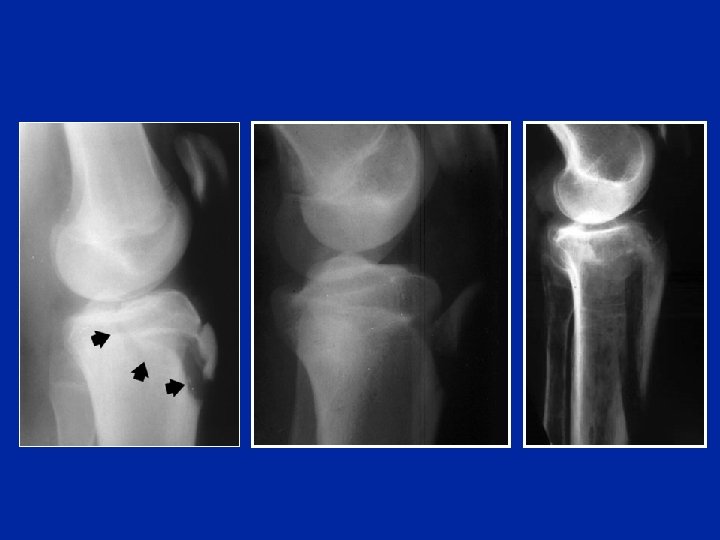

Fracturas-avulsiones de la tuberosidad tibial anterior en los niños Estadios de Ogden Tipo 1 Tipo 2 Tipo 3

Tipo 3 Necesidad de verificar la integridad del menisco

Tratamiento quirúrgico: osteosíntesis con tornillo

Ejemplos de osteosíntesis de la tuberosidad tibial anterior